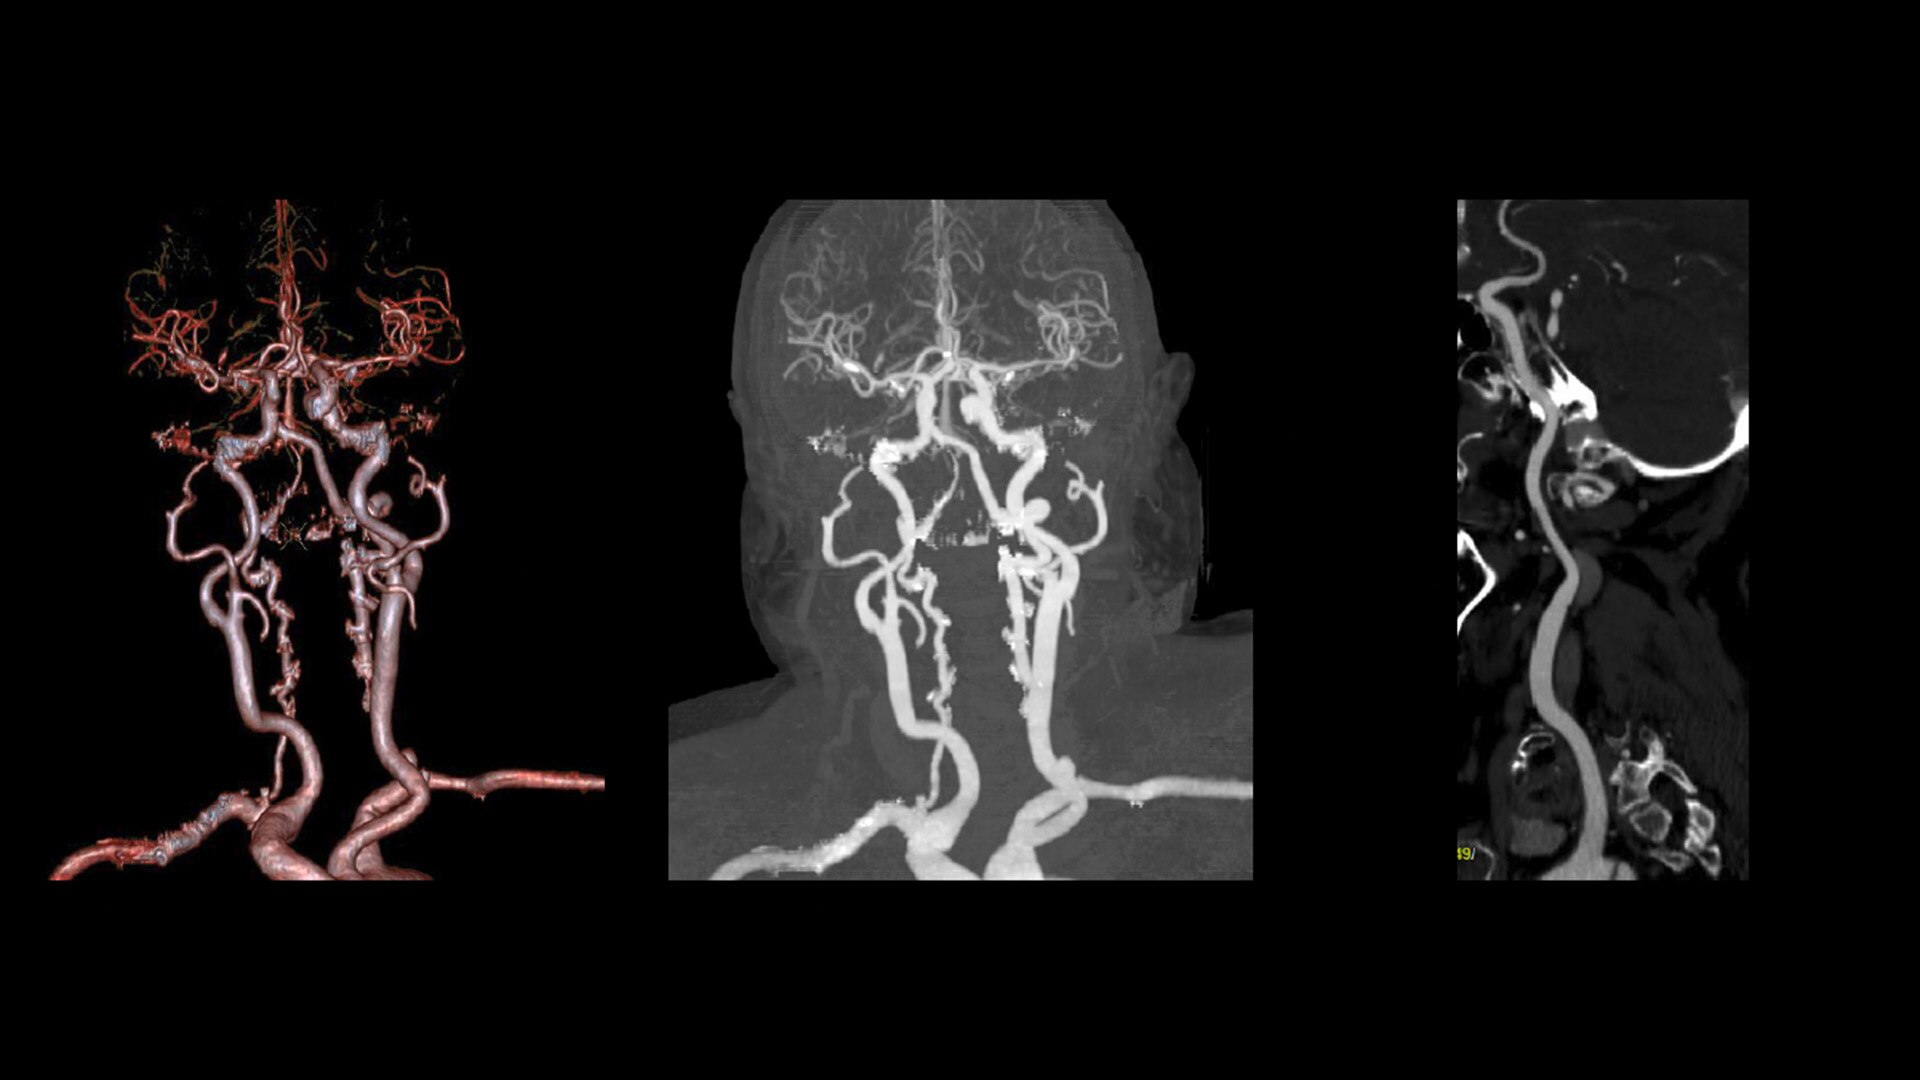

At the heart of Revolution Advance is a high-performance, reliable imaging chain with 42 kW of generator power, a 3.5 MHU X-ray tube and integrated detectors that reduce signal-to-noise by 20%2. This is paired with our smart, dose-reducing reconstruction applications like ASiR2, which can provide up to 40% lower dose while maintaining high image quality2.

When it comes to imaging more challenging cases, such as neuro, oncology or pediatric patients, VISR3. (Volumetric Image Space Reconstruction) reduces noise without impacting image resolution. This means less dose for the patient while maintaining the high-image quality you need for more accurate diagnoses.